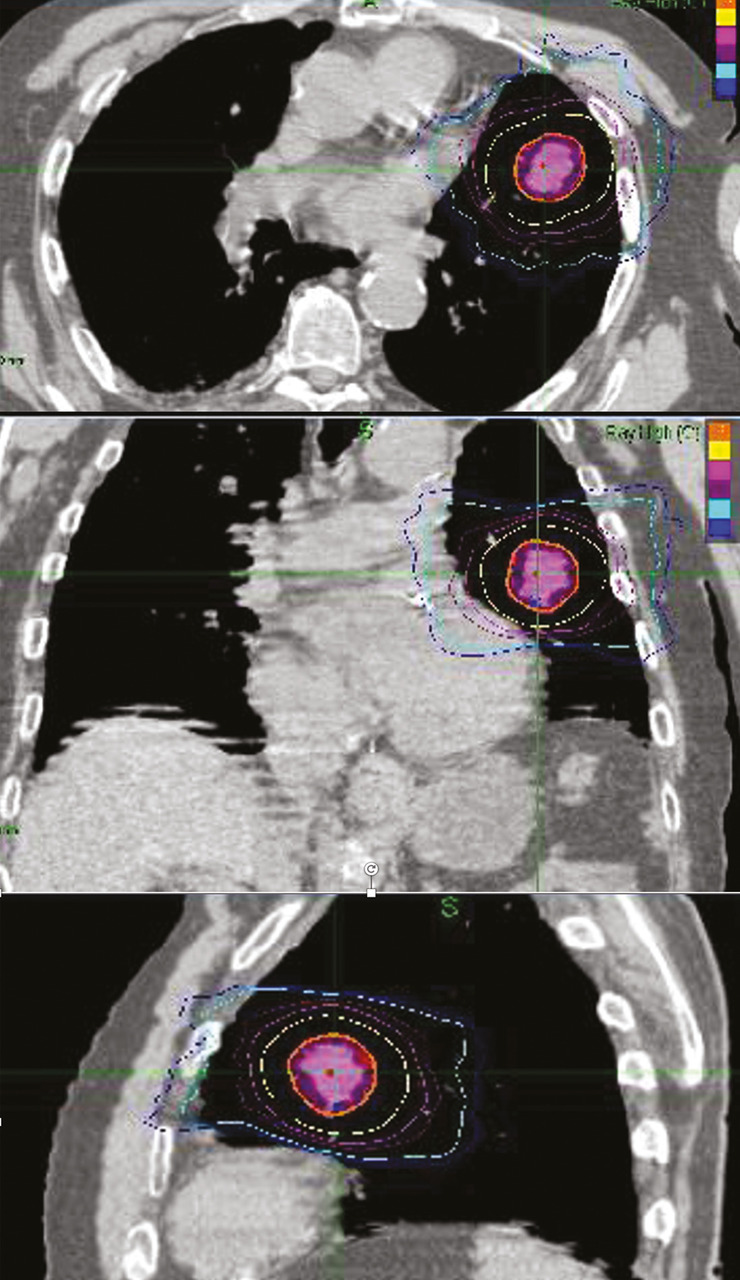

Radiothérapie en conditions stéréotaxiques

La radiothérapie en conditions stéréotaxiques (SBRT) consiste à délivrer une forte dose d’irradiation en moins de dix séances avec une haute précision dans un volume cible restreint (lésion de moins de 5 cm et pas plus de trois lésions synchrones).16 C’est une technique de haute précision demandant une expertise et un équipement particulier au sein des départements de radiothérapie. Elle peut être réalisée sur un accélérateur classique mais adaptée aux conditions stéréotaxiques ou sur un appareil dédié (Cyberknife  ; fig. 3). Elle n’est pas encore disponible dans toutes les indications dans tous les centres. Ainsi, il faut tenir compte de l’accessibilité au centre de traitement, qui peut nécessiter quelques aménagements logistiques pour les patients les plus âgés ou les plus dépendants. Cependant, le faible nombre de séances en fait un traitement particulièrement attractif chez le sujet âgé, même si la durée de la séance peut être plus longue et l’implantation de fiduciels parfois indispensable. Elle est une alternative à la chirurgie pour les cancers bronchiques non à petites cellules T1 -T2N0M0.17 Elle est aussi particulièrement utile dans la prise en charge des métastases cérébrales en limitant les altérations cognitives en comparaison de l’irradiation de l’encéphale en totalité, quel que soit l’âge. Elle se développe significativement dans les cancers de la prostate localisés de faible risque et dans les cancers du rein. Cependant, peu de données sont actuellement disponibles concernant la toxicité tardive et la qualité de vie chez les patients très âgés traités par SBRT.